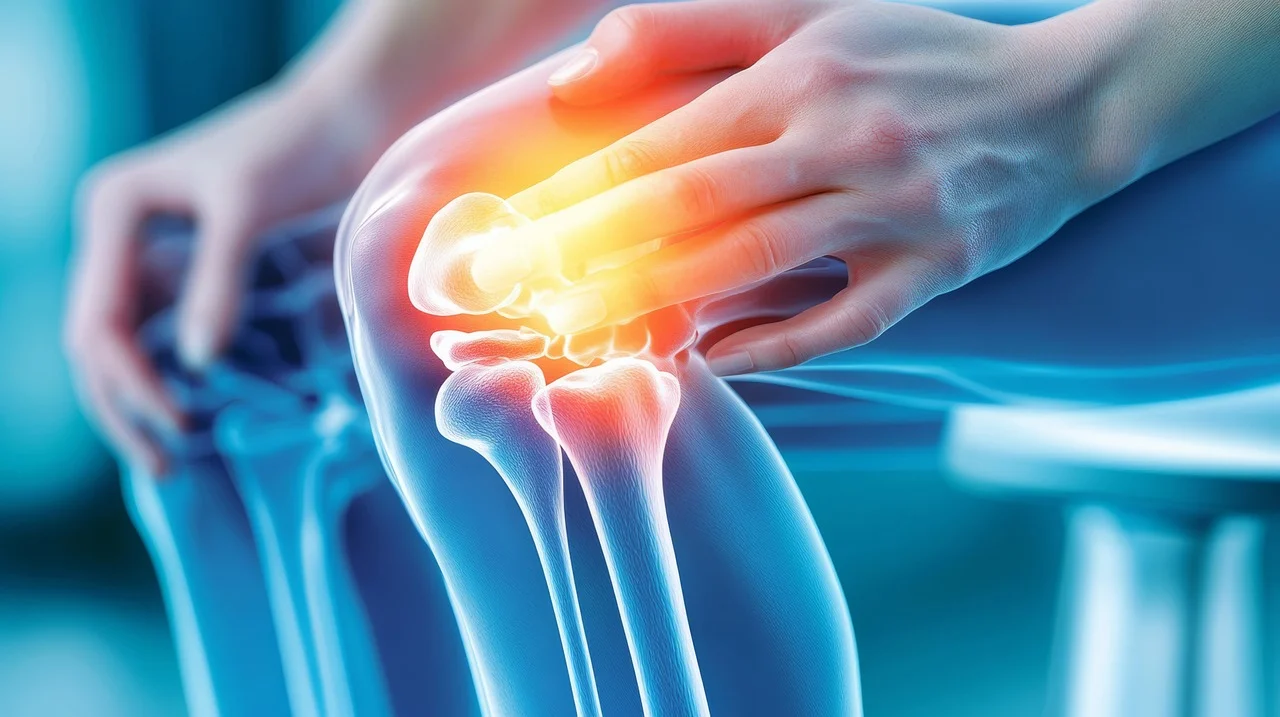

아침에 일어날 때마다 무릎이나 어깨가 뻣뻣하고 쑤시나요? 관절 통증 때문에 일상생활이 불편하게 느껴지셨다면, 아마도 연골 건강에 문제가 생긴 건 아닐까 걱정될 수 있습니다. 우리 몸의 관절을 보호하는 연골은 나이가 들거나 과도하게 사용하면서 점차 닳아 없어지기 쉽습니다. 하지만 다행히도 손상된 연골 건강을 되찾고 관절 통증을 줄이는 데 도움을 줄 수 있는 성분이 있습니다. 바로 콘드로이친이죠.

콘드로이친(Chondroitin)은 우리 몸의 연골, 인대, 힘줄, 피부 등 결합 조직에 풍부하게 존재하는 성분입니다. 특히 연골의 주요 구성 성분 중 하나인 프로테오글리칸을 구성하는 핵심 성분이죠. 연골은 관절의 충격을 흡수하고 뼈와 뼈 사이의 마찰을 줄여주는 쿠션 역할을 하는데, 이 연골의 탄력성과 수분 유지를 돕는 것이 바로 콘드로이친입니다.

콘드로이친은 우리 몸에서 자연적으로 생성되지만, 나이가 들면서 그 생성량이 점차 줄어들게 됩니다. 이렇게 콘드로이친이 부족해지면 연골이 약해지고 수분을 잃어 탄력성을 잃게 되며, 결국 연골이 손상되어 관절 통증과 염증을 유발하는 퇴행성 관절염으로 이어질 수 있어요.